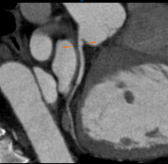

Chẩn đoán hình ảnh mô mềm tiên tiến cho vùng bụng.

Tăng cường độ tương phản I-ốt.

Hỗ trợ đánh giá an toàn cho bệnh nhân.

Đảm bảo hình ảnh chất lượng cao.